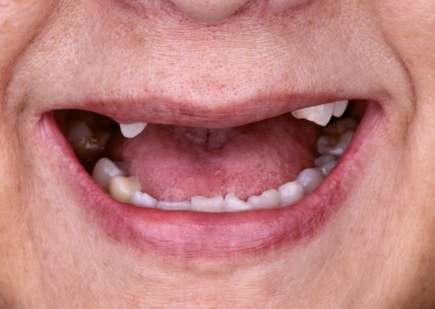

Presentación del caso

Paciente femenino de 61 años de edad, acude al Posgrado de Prostodoncia e Implantología de la Universidad de la Salle Bajío remitida por su médico general del Seguro Social para saneamiento y rehabilitación de su condición oral. La paciente es

no fumadora y refiere antecedentes de adenocarcinoma, quimioterapia, osteoporosis y la indicación de administrar bifosfonatos intravenosos. A pesar de sus antecedentes, su médico consideró pertinente realizar su tratamiento dental.

Al examen físico, extraoralmente la paciente no presentaba ninguna anomalía, agrandamiento o signo importante de algún problema clínico. Intraoralmente se encontraba sana peridontalmente, sin embargo, presentaba caries y restauraciones de amalgama con filtración en el sector postero superior y postero inferior. Se observaba una prótesis fija de 5 unidades en sector anterosuperior con desajuste y fractura de muñones.

Basándonos en el examen clínico y radiográfico, se opta por retirar la prótesis fija superior y realizar las extracciones de los dientes fracturados, así como la eliminación de caries y cambio de amalgamas. Se realiza fase de saneamiento eliminando caries y restauraciones defectuosas, dando lugar así a un edentulismo parcial de la arcada superior (Fig. 1a, 1b). Después de efectuar el diagnóstico y anamnesis se decide no colocar implantes y hacer una prótesis removible retenida por coronas telescópicas friccionales.